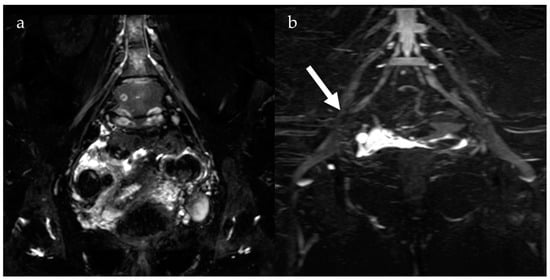

2.1. Endometrioma

4. Diffusion-Weighted Imaging

- Busard, M.P.H.; Mijatovic, V.; van Kuijk, C.; Bos, I.P.D.; Hompes, P.; van Waesberghe, J. Magnetic resonance imaging in the evaluation of (deep infiltrating) endometriosis: The value of diffusion-weighted imaging. J. Magn. Reson. Imaging 2010, 32, 1003–1009. [Google Scholar] [CrossRef] [PubMed]

- Balaban, M.; Idilman, I.S.; Toprak, H.; Unal, O.; Ipek, A.; Kocakoc, E. The utility of diffusion-weighted magnetic resonance imaging in differentiation of endometriomas from hemorrhagic ovarian cysts. Clin. Imaging 2015, 39, 830–833. [Google Scholar] [CrossRef] [PubMed]

- Moteki, T.; Horikoshi, H.; Endo, K. Relationship between apparent diffusion coefficient and signal intensity in endometrial and other pelvic cysts. Magn. Reson. Imaging 2002, 20, 463–470. [Google Scholar] [CrossRef]

- Singh, A.; Das, C.J.; Das, B.K.; Gupta, A.K. Utility of diffusion weighted imaging in diagnosing subdiaphragmatic endometriosis presenting as shoulder pain. Indian J. Radiol. Imaging 2017, 27, 314–317. [Google Scholar] [CrossRef]